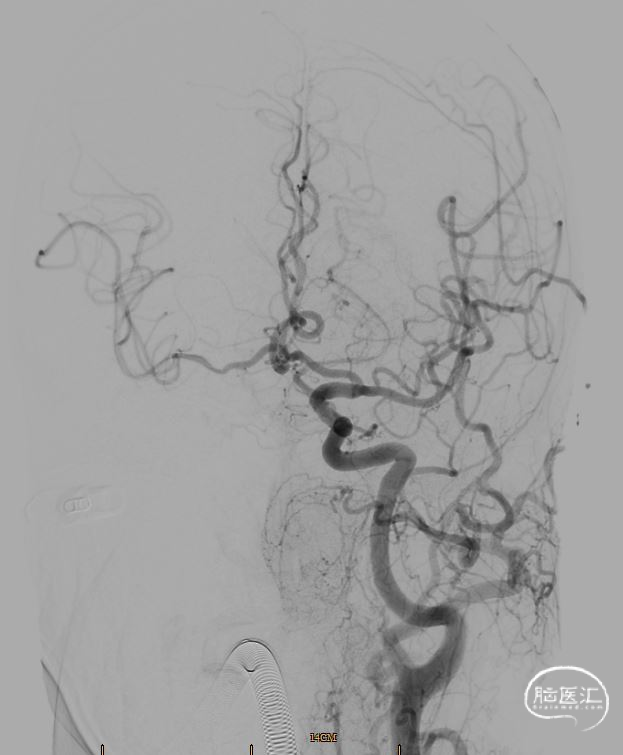

沿微导管送入取栓支架(6mm*30mm),准确对位后成功释放,撤出微导管,造影提示右侧颈内动脉及右侧大脑中动脉有前向血流,等待5分钟后,跟进颅内支持导管至颈内动脉C2段,缓慢回撤取栓支架,并沿中间导管抽吸,可见支架缠绕少量血栓,送入Synchro-2 微导丝3m至C7段,回撤中间导管,再次造影提示右侧颈内动脉C1段重度狭窄伴夹层样改变,观察10分钟血流较前减慢。

撤除中间导管,沿微导丝送入Viatrac 14球囊(4*30mm),在球囊的引导下,将6F 长鞘送至颈动脉C2段远端,撤出球囊。

球囊输送系统带6F 长鞘通过病变(特洛伊木马技术),撤出球囊后,6F 长鞘带Xpert Pro支架输送系统通过病变 。

再次沿导丝送入Xpert Pro(6X40mm)支架,回撤长鞘,对位准确后成功释放支架,再次造影提示支架贴壁良好,前向血流通畅(TICI分级3级)。